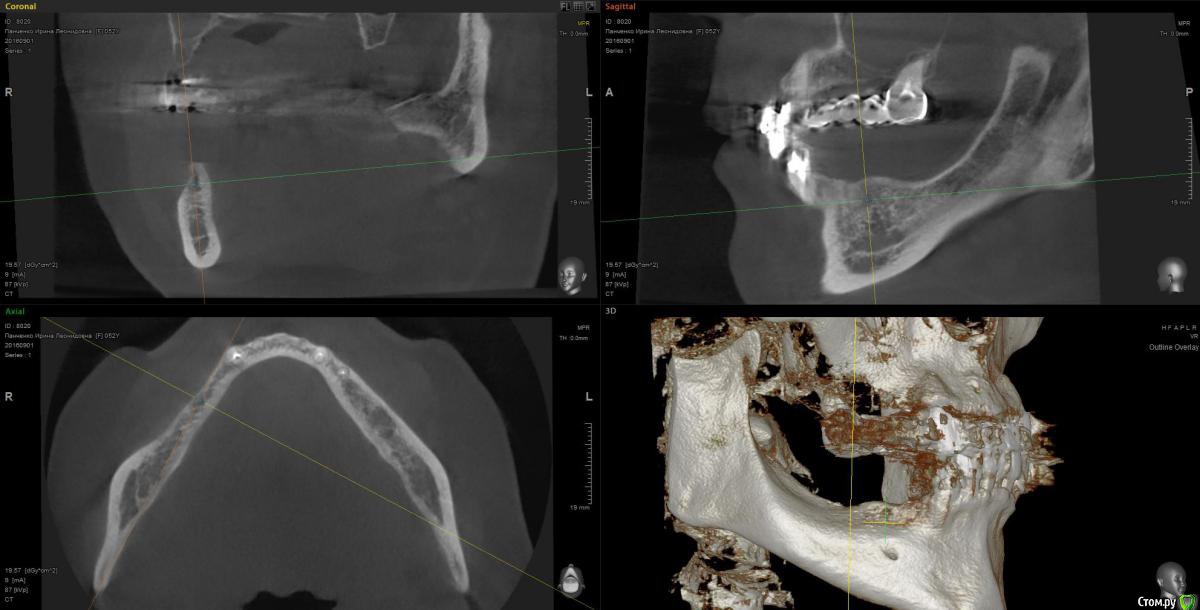

Kostoprav Опубликовано 13 марта, 2017 Поделиться Опубликовано 13 марта, 2017 рецепт сосиски: 70%биопласт by владмива +30%аутокость, мембрана hyprosorb кт до кт сразу после имплантации кт через пол года 3 Ссылка на комментарий

Kostoprav Опубликовано 14 марта, 2017 Автор Поделиться Опубликовано 14 марта, 2017 по порядку 8 Ссылка на комментарий